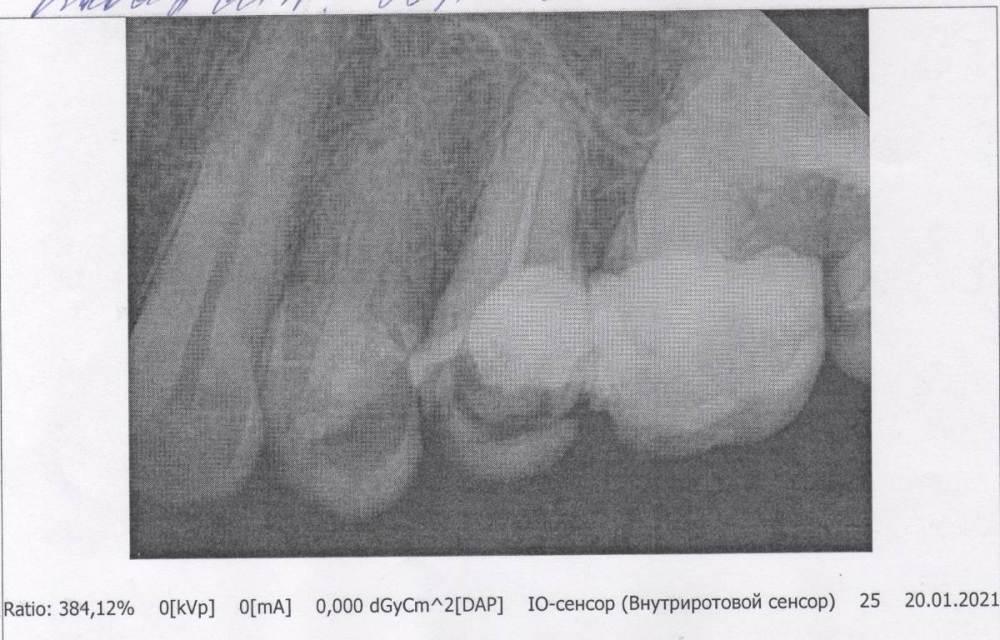

laz2000 Опубликовано 27 марта, 2021 Автор Поделиться Опубликовано 27 марта, 2021 (изменено) Взял в поликлинике снимки, выкладываю первый 1 снимок 25 зуб от 20.01.21 ( пояснение: врач должна была запломбировать каналы 25 зуба, остальные зубы, кот видны на снимке, еще не лечены) Вопрос все тот же: запломбированы ли каналы 25 зуба, если можно ответьте пожалуйста. Изменено 27 марта, 2021 пользователем laz2000 Ссылка на комментарий

ЛанаМ Опубликовано 30 марта, 2021 Поделиться Опубликовано 30 марта, 2021 (изменено) Каналы 25 зуба запломбированы. Качество пломбирования оценить сложно. Я так понимаю, снимок распечатан на бумаге на обычном принтере. В этом случае детали смазываются и нет четкости. Изменено 30 марта, 2021 пользователем ЛанаМ Ссылка на комментарий